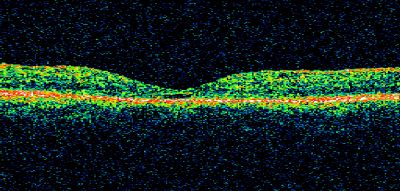

Macular Hole Closed with Vitrectomy - Post-op 20/60 Vision

Macular Hole

closed

vitrectomy